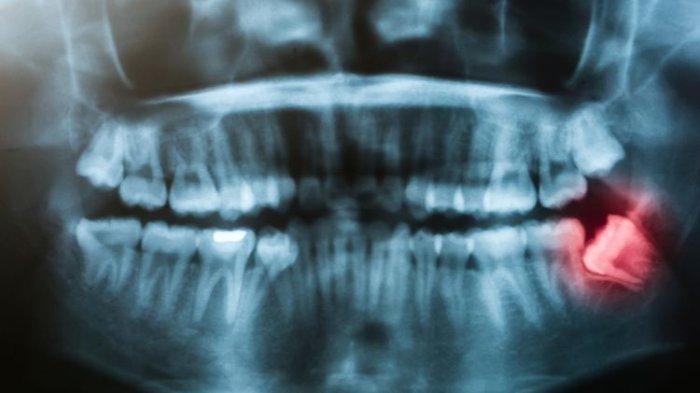

TRIBUNHEALTH.COM - Jika terjadi impaksi gigi akan sangat mengganggu saat pengunyahan.

Tentu saja gigi yang mengalami impaksi tersebut harus diambil.

Terjadinya impaksi gigi bisa berpengaruh tehadap kesehatan lain.

Misalnya keluhan impaksi gigi yang menekan saraf akan menimbulkan rasa nyeri, telinga mendengung, dan rasa punggung yang tidak nyaman.

Impaksi gigi dengan posisi tidur, maka akan menyebabkan gigi yang berada di depannya mengalami kerusakan.

Gigi geraham yang tumbuh miring, hampir 80-90% menimbulkan infeksi.

Dokter akan melakukan pemeriksaan terlebih dahulu, mulai dari pemeriksaan klinis atau secara langsung maupun pemeriksaan rontgent.

Apabila giginya sudah tumbuh semppurna namun miring, hanya dilakukan pencabutan biasa.

Tetapi jika ada sedikit tekanan didalam tulang ataupun gusi, maka dokter akan mengindikasikan ke arah operasi.